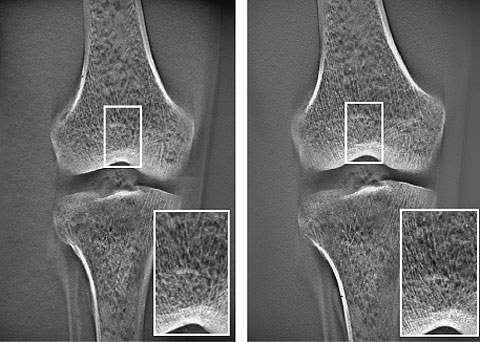

Air calibration periodically conducts one normal tomosynthesis operation for each field size to acquire the optimal calibration data for each tomosynthesis scan trajectory in order to improve the graininess. Fig. 14 shows images before and after introduction of the software. The graininess of the overall image has clearly improved. This overcomes the problems at the thinnest image reconstruction slice thickness setting, and we currently use this setting without any problems.